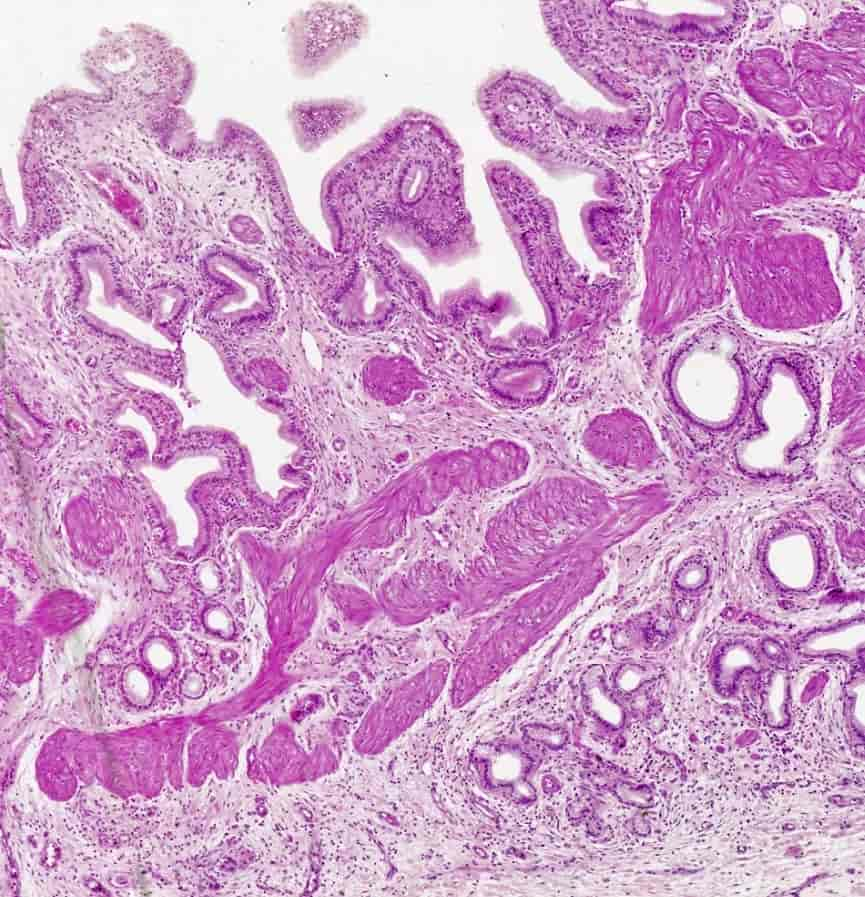

Galleveiene på rosa bileteleveren delvis gjennomskåret.